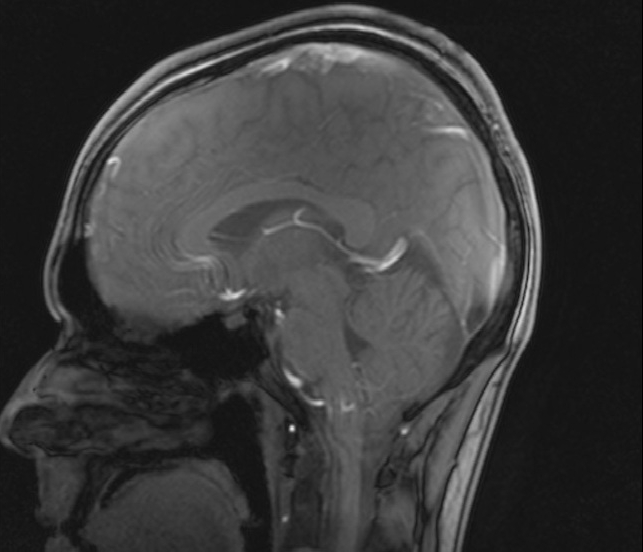

So sieht das Gehirn unseres Redakteurs also von innen aus. Foto: privat

Medizinische Forschung am Menschen ist wichtig und riskant. Ein persönlicher Einblick in die Hintergründe klinischer Studien

Dort würde ich Luft atmen, die statt der gewohnten 21 nur zwölf Prozent Sauerstoff enthält. Dies entspricht in etwa den Verhältnissen in einer Höhe von 4000 Metern über dem Meeresspiegel. Durch den einhergehenden Sauerstoffmangel, so die Forschungshypothese, würden die Wände der Blutgefäße des Gehirns undicht und daher Blut und Hirnwasser vermischt. Um dies zu prüfen, würden vorher und nachher MRT-Aufnahmen meines Kopfes gemacht.  Bei etwa der Hälfte der Probanden sei außerdem mit Symptomen der akuten Höhenkrankheit zu rechnen.

Trotz eines leicht mulmigen Gefühls begebe ich mich also in die Sportmedizinische Ambulanz der Krehl-Klinik, es ist Samstagnachmittag. Während andere Studenten sich für das abendliche Ausgehen wappnen, lasse ich die ersten Voruntersuchungen über mich ergehen. Kurz darauf liege ich bereits zum ersten Mal in einem Tomographen. Dessen Röhre ist noch enger als ich vermutet hatte. Und laut wird es in ihr auch: Ein MRT (Magnetresonanztomograph) arbeitet mit starken Magnetfeldern. Die dafür benötigten Stromstärken produzieren einiges Geräusch. Nach einer Weile fühle ich mich, als läge ich auf einem U-Bahn-Schacht.

Am nächsten Morgen sehne ich die abschließende MRT-Aufnahme förmlich herbei. Mittlerweile ist mir vollauf bewusst, wofür man das scheinbar leicht verdiente Probandenentgelt erhält. Nicht dass ich meine Teilnahme an der Studie bereuen würde, aber erneut teilnehmen werde ich wohl nicht. Kurz darauf werde ich in einem Rollstuhl Richtung MRT geschoben, neben mir ein riesiger Blasebalg. Durch diesen werde ich auch weiterhin mit sauerstoffarmer Luft beatmet. In den Gängen der Klinik werde ich misstrauisch beäugt; ich muss ziemlich miserabel aussehen. Eine halbe Stunde später jedoch ist alles überstanden. Zum ersten Mal seit zwölf Stunden kann ich wahrhaft durchatmen. Ein wunderschönes Gefühl. Nach diesem Erlebnis beschleicht mich jedoch erneut die Frage: Wozu das Ganze? Wofür, außer als neues Facebook-Profilbild, taugen 2000 Fotos meines Gehirns? Kurz: Hat sich der Aufwand gelohnt?